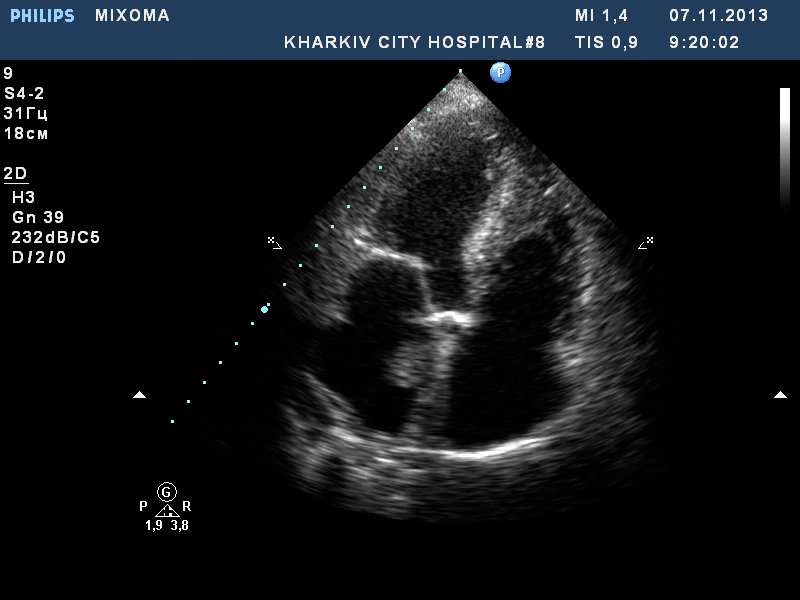

миксома ЛП

у пациентки миксома, аортальный стеноз с недостаточностью, дилатация левого предсердия, гипертрофия ЛЖ.